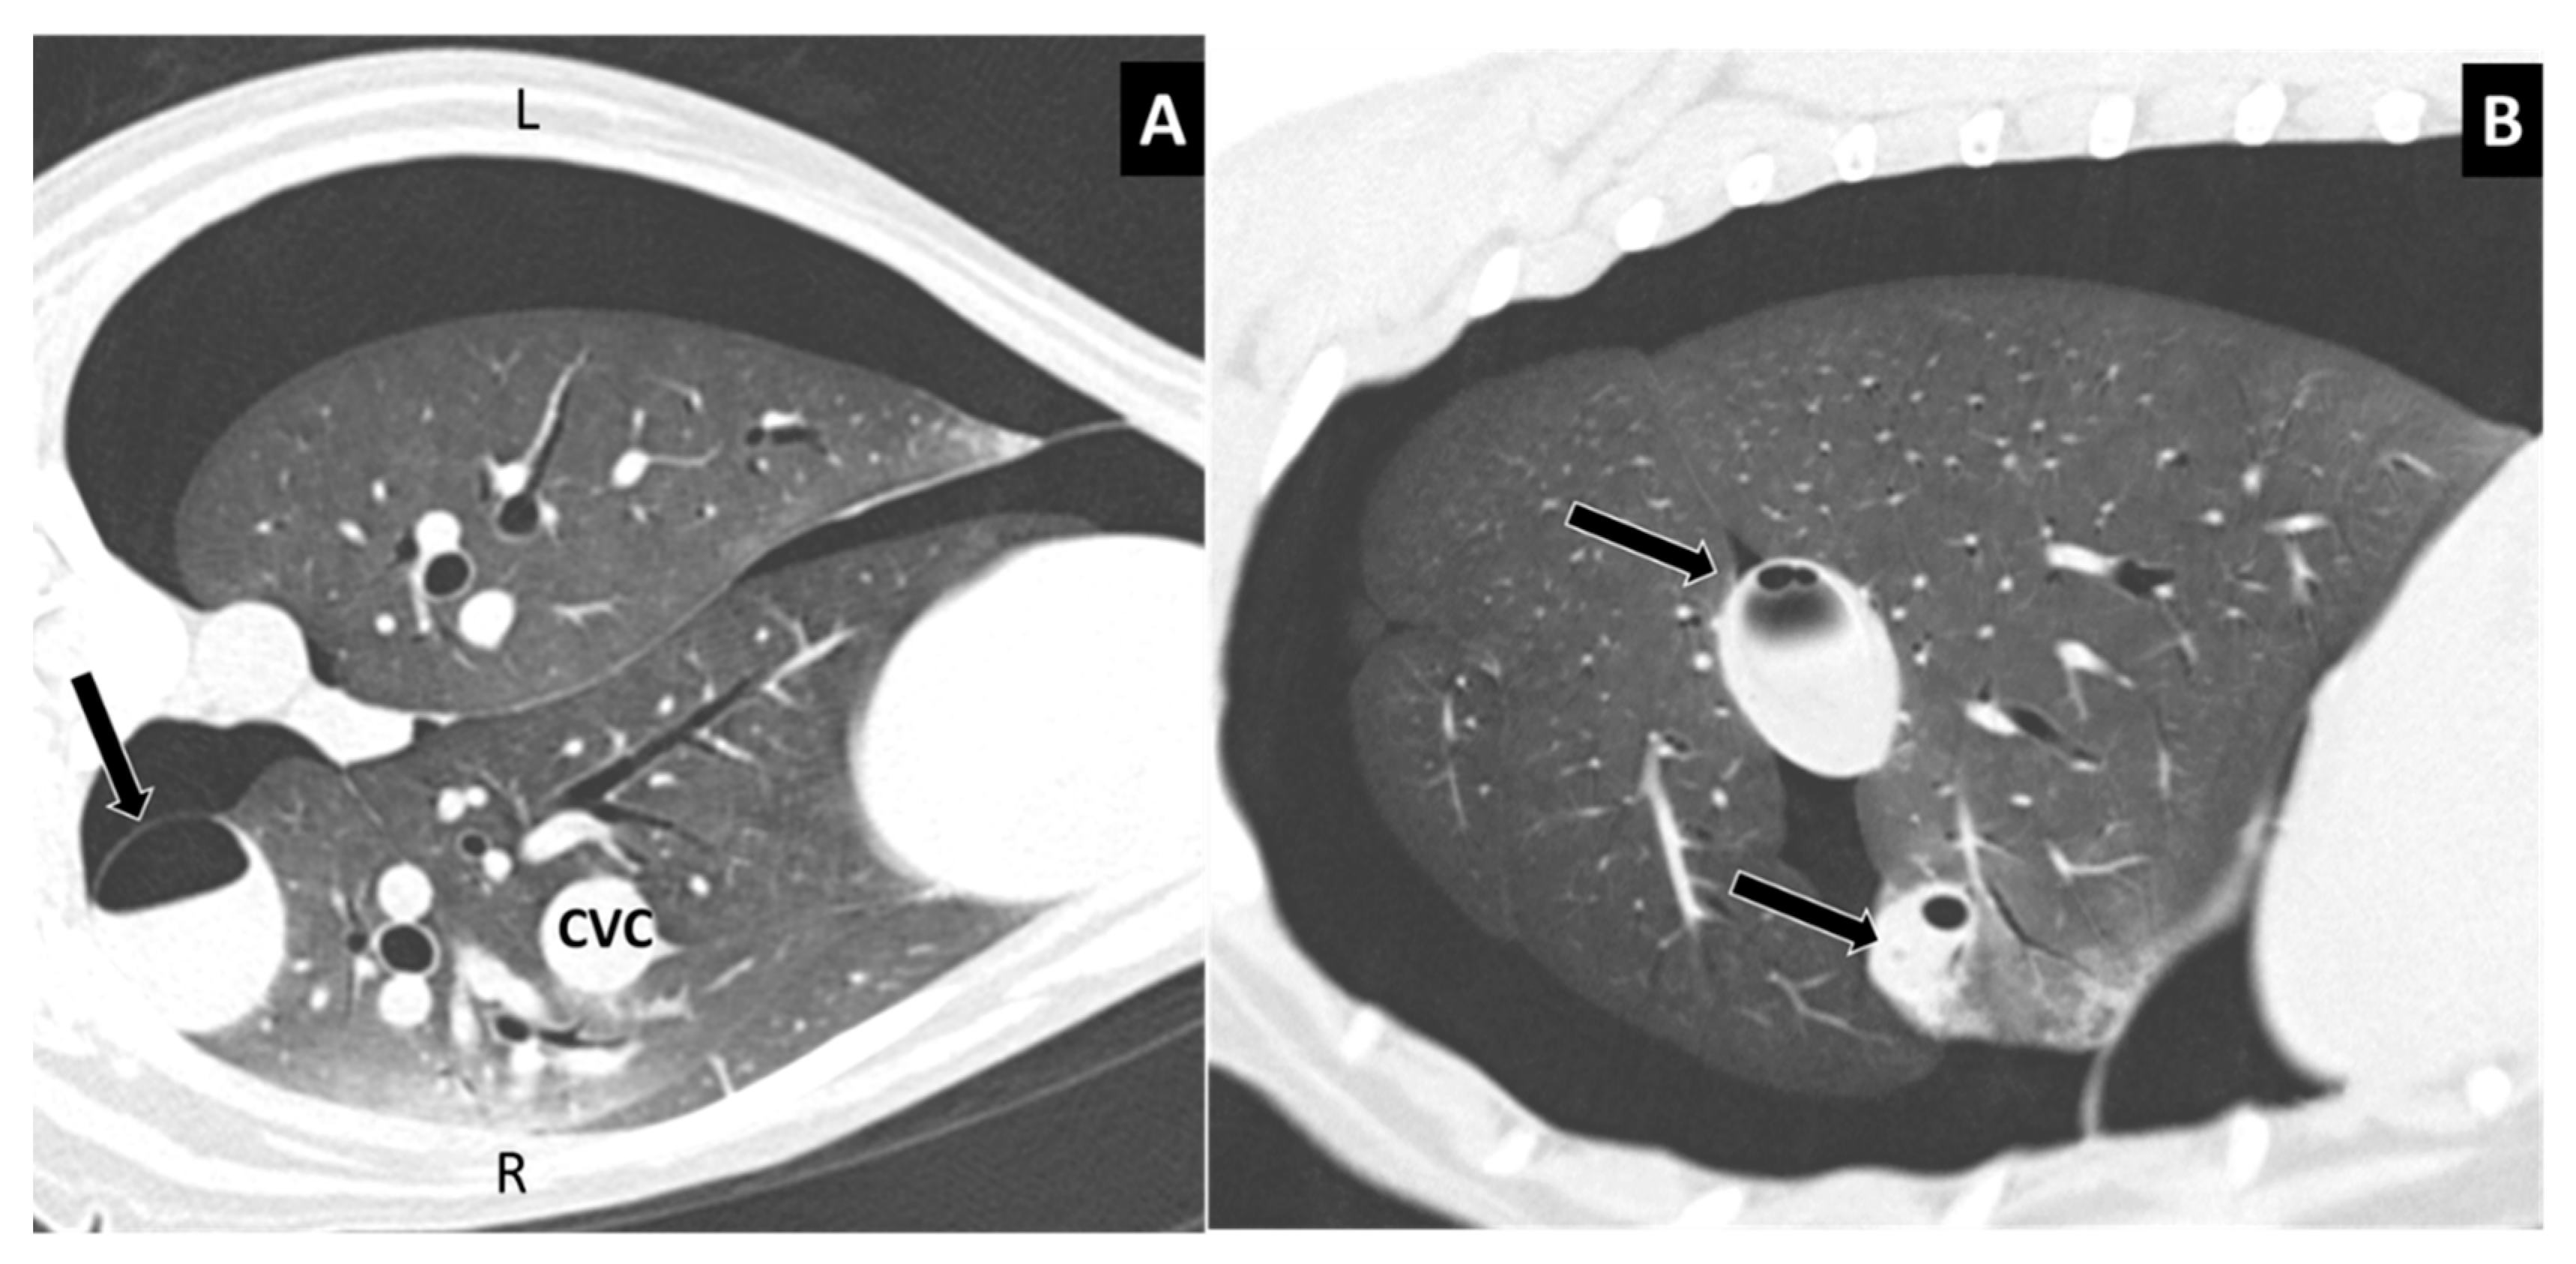

Figure 6.

(A) Large subpleural, paravertebral lesion in a dog, without evidence of vertebral fracture (Type 2) (arrow). The lesion contained blood and air. Note the bilateral pneumothorax. (B) Left parasagittal view in the same dog, showing two lesions around an interlobar fissure, almost completely filled with blood.

One or more follow-up CT studies were available in four cases from 2 days to one month after the initial CT examination. In follow-up CT studies, lesions showed increasing fluid content over time (Figure 7). Complications of lung lacerations were observed in two cases. One dog showing several lung lacerations in the right caudal lobe one hour after trauma underwent lobectomy few days after admission for the abscessation and pneumonic involvement of that lobe. Another dog showed a lung collapse due to massive pneumothorax for a ruptured subpleural lung laceration (Figure 8). In this case, a chest drainage system placed for few days allowed the lung to be pulled up against the parietal pleura and the dog was discharged to its home in a stable condition.

Figure 7.

Comparison of computed tomography (CT) images of the left lung in a traumatized dog with Type 2 and Type 4 lung lacerations. (A) The first CT examination showed two cystic, air-containing lesions and ipsilateral pneumothorax (without rib or vertebral fractures). (B) After 5 days, CT showed air–fluid levels in both lesions and a small amount of air visible in the pleural cavity.